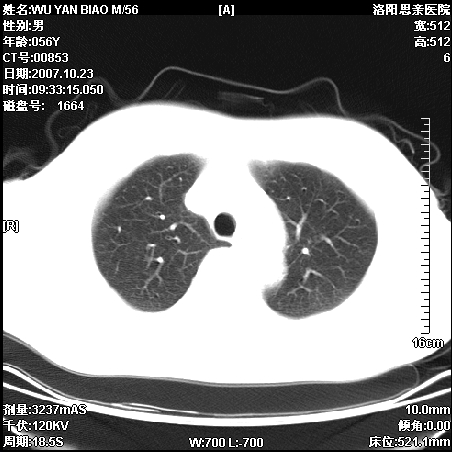

标题: CT10160:M56Y,体检发现,病人无不适,病人随访中 [打印本页]

标题: CT10160:M56Y,体检发现,病人无不适,病人随访中

后上纵隔占位,与肺交界清,宽基底附着脊柱,密度均匀,局部骨质无明确改变.

考虑;神经源性肿瘤,---起源交感n链?,不除外肠源性囊肿.

1、病灶在后纵隔脊柱旁沟内,此处是神经原性肿瘤的好发部位

2、病灶边缘光滑整齐,更说明病灶来于纵隔,由于有胸膜的包裹所以才导致这么光滑的边缘

3、病灶内的密度均匀